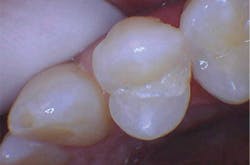

With the help of magnification, we are able to prepare small Class II lesions without sacrificing the marginal ridge, ensuring the longevity of our restoration and maximizing the remaining tooth structure with this minimally invasive approach (figures 3a–3d).

Figures 3a–3d: Minimally invasive Class II preparation with marginal ridge preservation